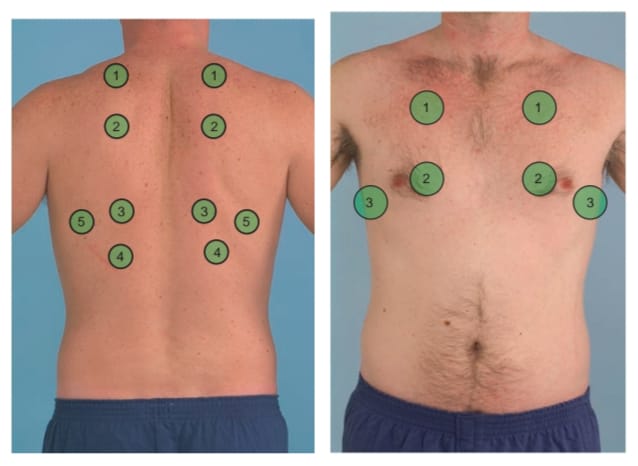

Auscultation (અસ્કલટેશન):

- અસ્કલટેશનમાં સ્ટેથોસ્કોપની મદદથી લંગ સાઉન્ડ સાંભળવામાં આવે છે.

- સ્ટેથોસ્કોપની મદદથી નોર્મલ લંગ સાઉન્ડની કેરેક્ટરિસ્ટિક નોટ કરવી જેમ કે લોકેશન, ક્વોલિટી, ઇન્ટેન્સિટી

- આ ઉપરાંત કોઈપણ પ્રકારના એબનોર્મલ લંગ સાઉન્ડ સાંભળવા મળે છે કે નહીં તે અસ્કલટેટ કરવું.

- અસ્કલટેશનમાં ચેસ્ટની એન્ટેરિયર અને પોસ્ટેરીયર બાજુ ડાયાફ્રામની મદદથી લંગ સાઉન્ડ અસ્કલટેટ કરવામાં આવે છે. નીચે આપેલા પિક્ચરમાં દર્શાવ્યા મુજબ ચેસ્ટને અસ્કલટેટ કરવામાં આવે છે.

- ઇન્સ્પિરેશન અને એક્સપિરેશન બંને સમયે સાઉન્ડ નોટ કરવામાં આવે છે. વચ્ચે પેશન્ટને રેસ્ટ આપવામાં આવે છે જેથી હાઇપરવેન્ટિલેશનની કન્ડિશનની પ્રિવેન્ટ કરી શકાય.

- આમ અસ્કલટેશનની મદદથી એબનોર્મલ સાઉન્ડને ડિટેક્ટ કરવામાં આવે છે.

- આ ઉપરાંત અસ્કલટેશનમાં વોઇસ સાઉન્ડ (બ્રોન્કોફોની, ઇગોફોની) પણ નોટ કરવામાં આવે છે.